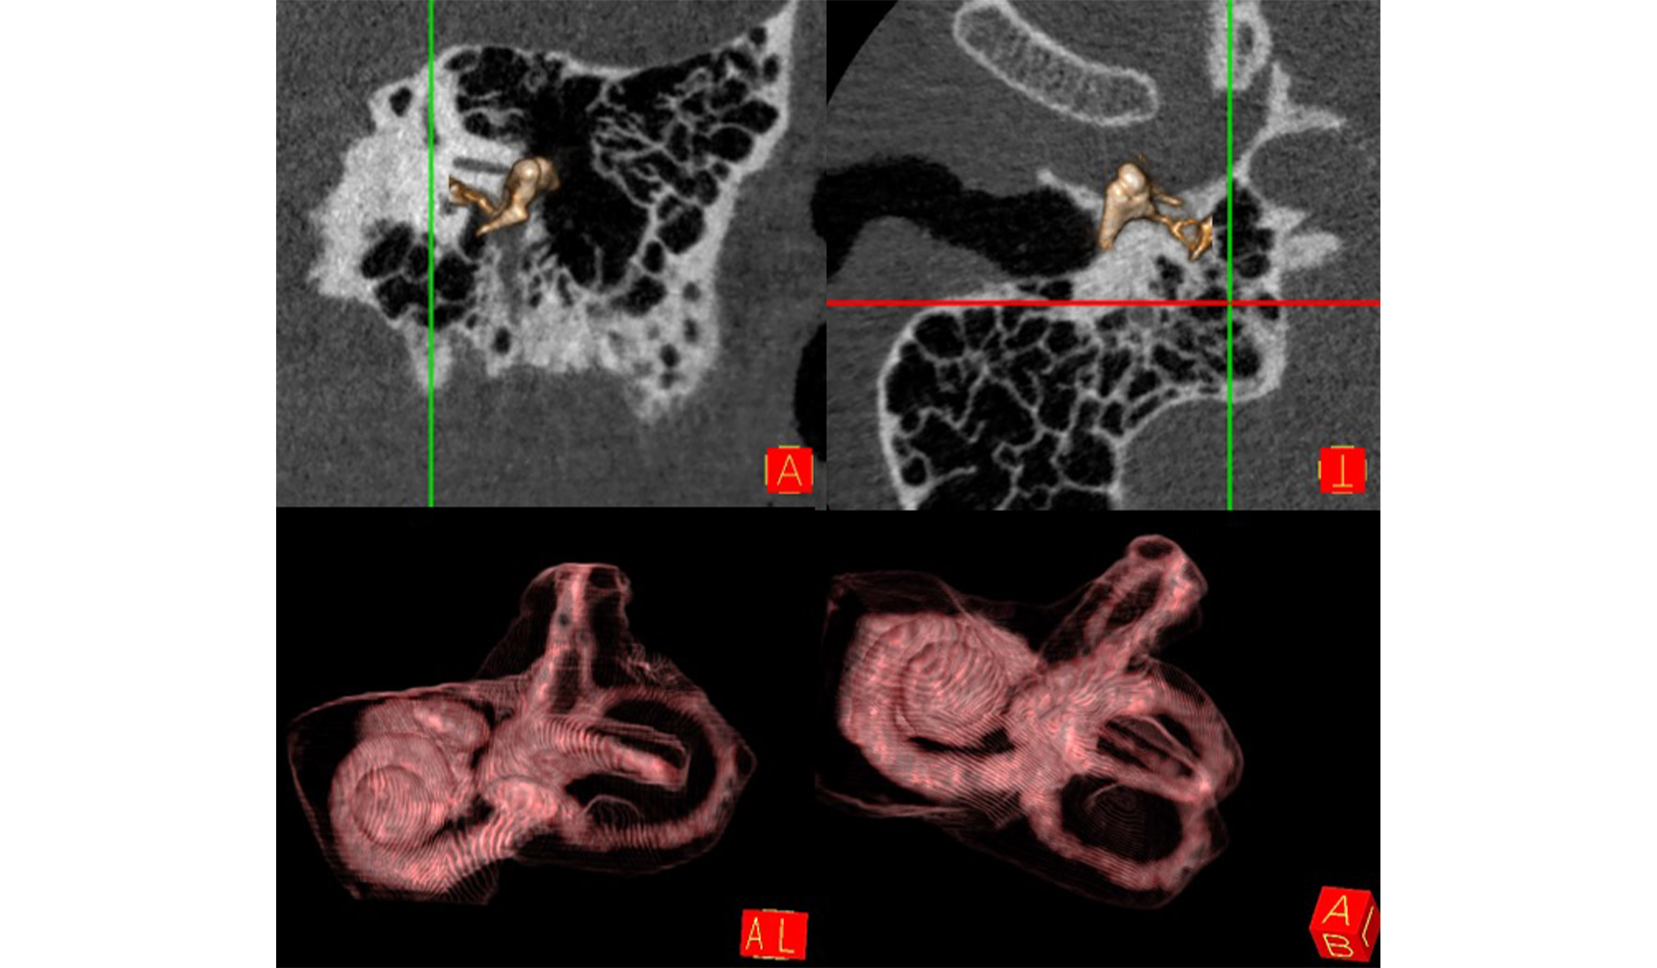

Cadena Osicular DER IZQ

Oído Interno (Cóclea y Canales Semicirculares) DER IZQ